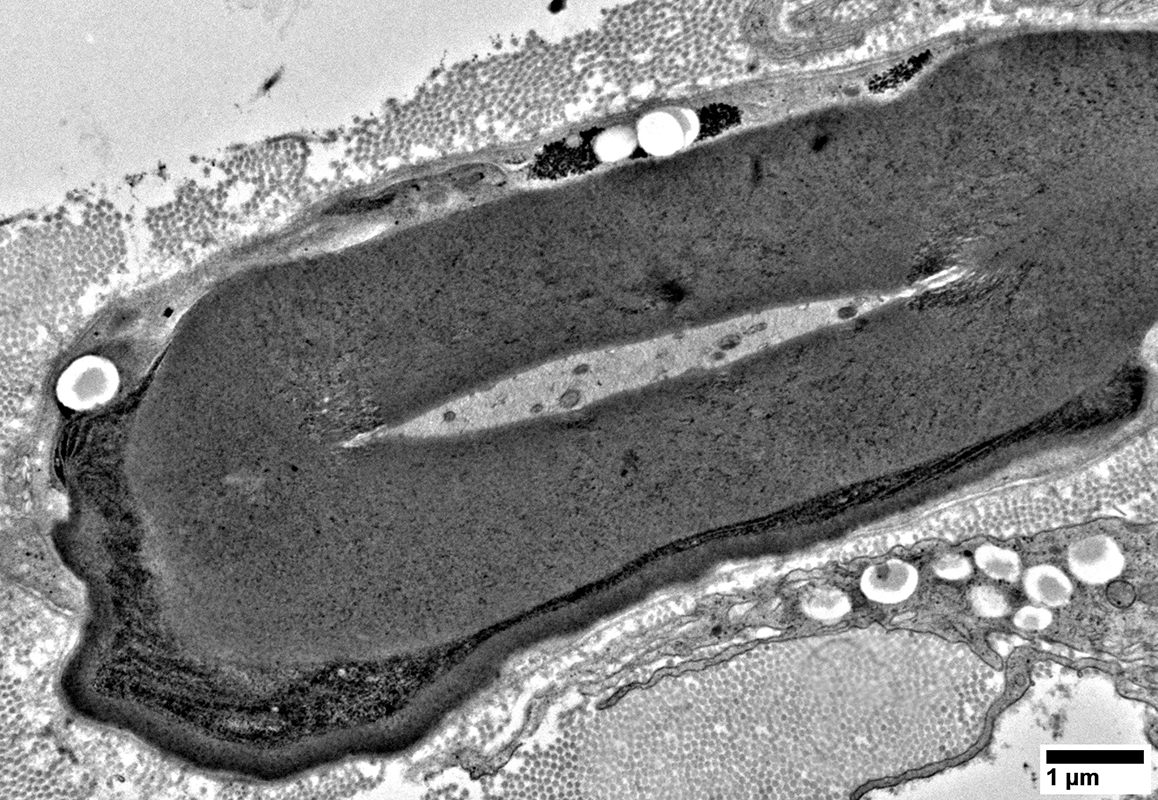

Axons: Large & Abnormal Structure with no surrounding Myelin

Axons surronded by thin Schwann cell processes containing Myelin, or Lipid, Debris

Axons surronded by multiple small Schwann cell processes

Axons surronded by layers of Schwann cell processes

Schwann cells around Axons: Contain Myelin Degradation Products